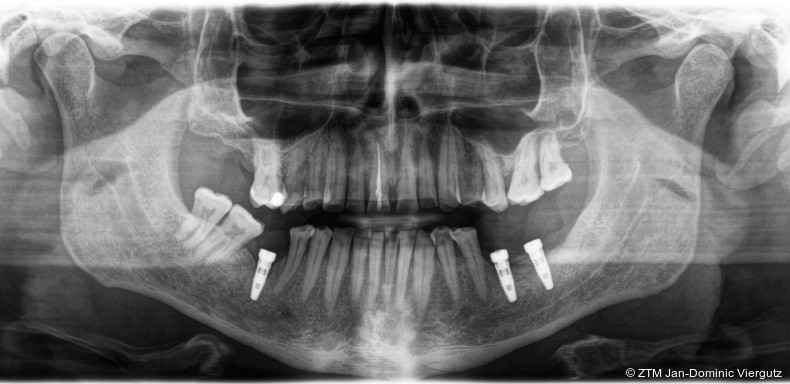

Um die Funktion und Ästhetik wiederherzustellen, wurde eine komplette Sanierung empfohlen, da die klinische Kronenlänge deutlich verkürzt und die Ästhetik eingeschränkt war. Eine Bisshebung war notwendig, um die ursprüngliche Vertikaldimension wiederherzustellen. Im Unterkiefer sollten drei Implantate im Seitenzahnbereich (36, 37, 46) mithilfe einer geführten Implantation gesetzt werden. Sämtliche Eingriffe wurden unter Narkose und in Anwesenheit eines Anästhesisten durchgeführt, um dem hohen Angstlevel des Patienten gerecht zu werden.

Nach der erfolgreichen Eingliederung der Michigan-Schiene (Erkodur, Erkodent) und dem deutlichen Rückgang der Kiefergelenkschmerzen wurde die Behandlung gemäß dem Therapieplan fortgesetzt. Zunächst erfolgte die erneute Wurzelbehandlung am Zahn 11, gefolgt von der schablonengeführten Implantation (DTX Studio Clinic, Nobel Biocare) von drei Implantaten (NobelReplace, Nobel Biocare) im Unterkiefer (36, 37 und 46). Alle chirurgischen Maßnahmen wurden in Dämmerschlaf-Narkose unter Begleitung eines Anästhesisten durchgeführt.